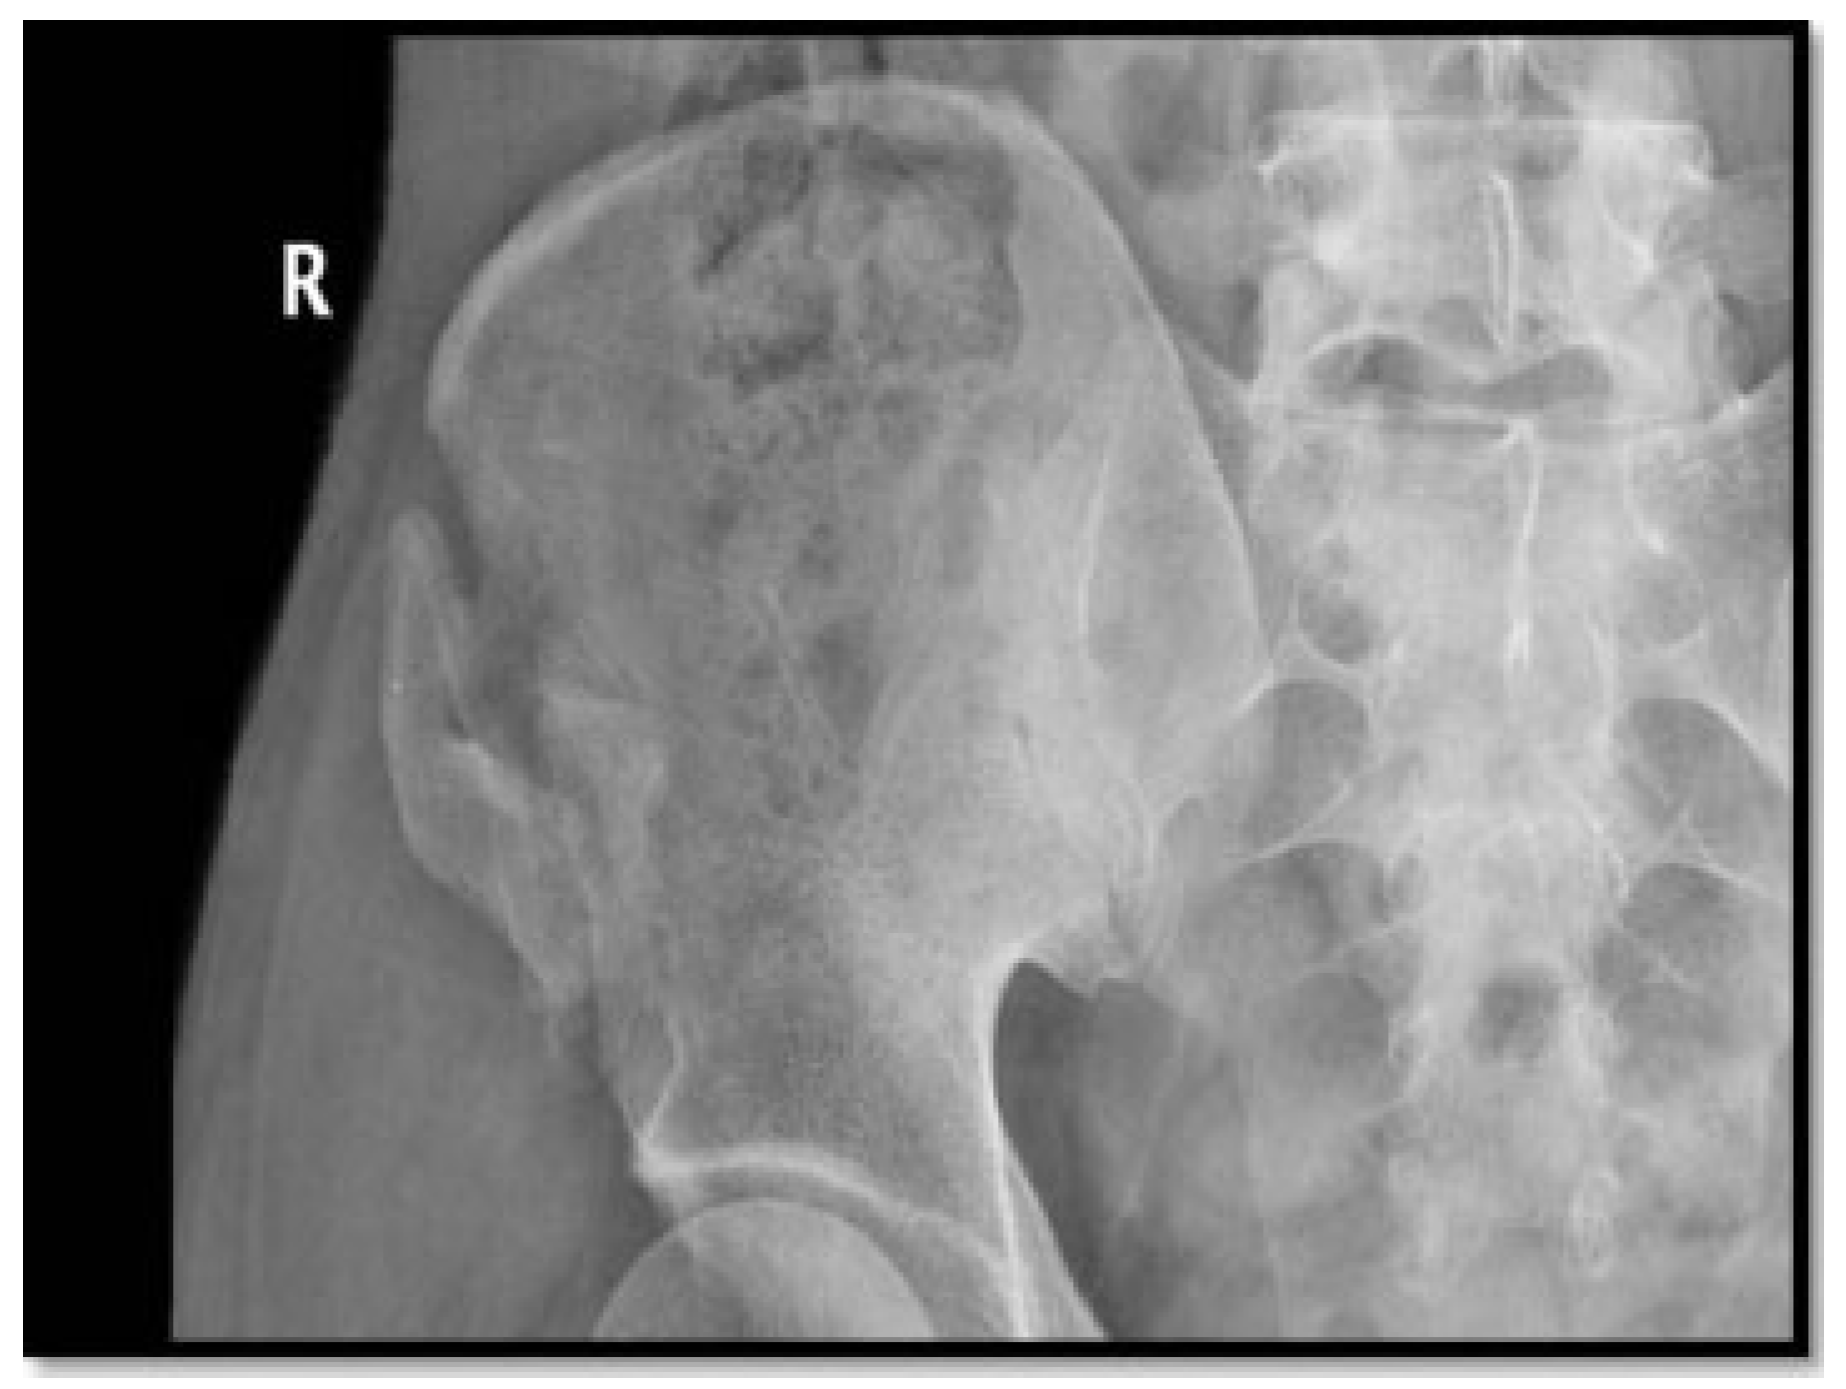

- Fractures: Of the 372 patients, 2 patients (0.538%) developed fracture iliac, 1 patient developed greenstick fracture of the iliac wing intraoperative and the case was managed with lag screw, and the other patient had the fracture iliac 25 days postoperative secondary to carrying 45 kg of sac of rise and he was managed conservatively (Figure 20).